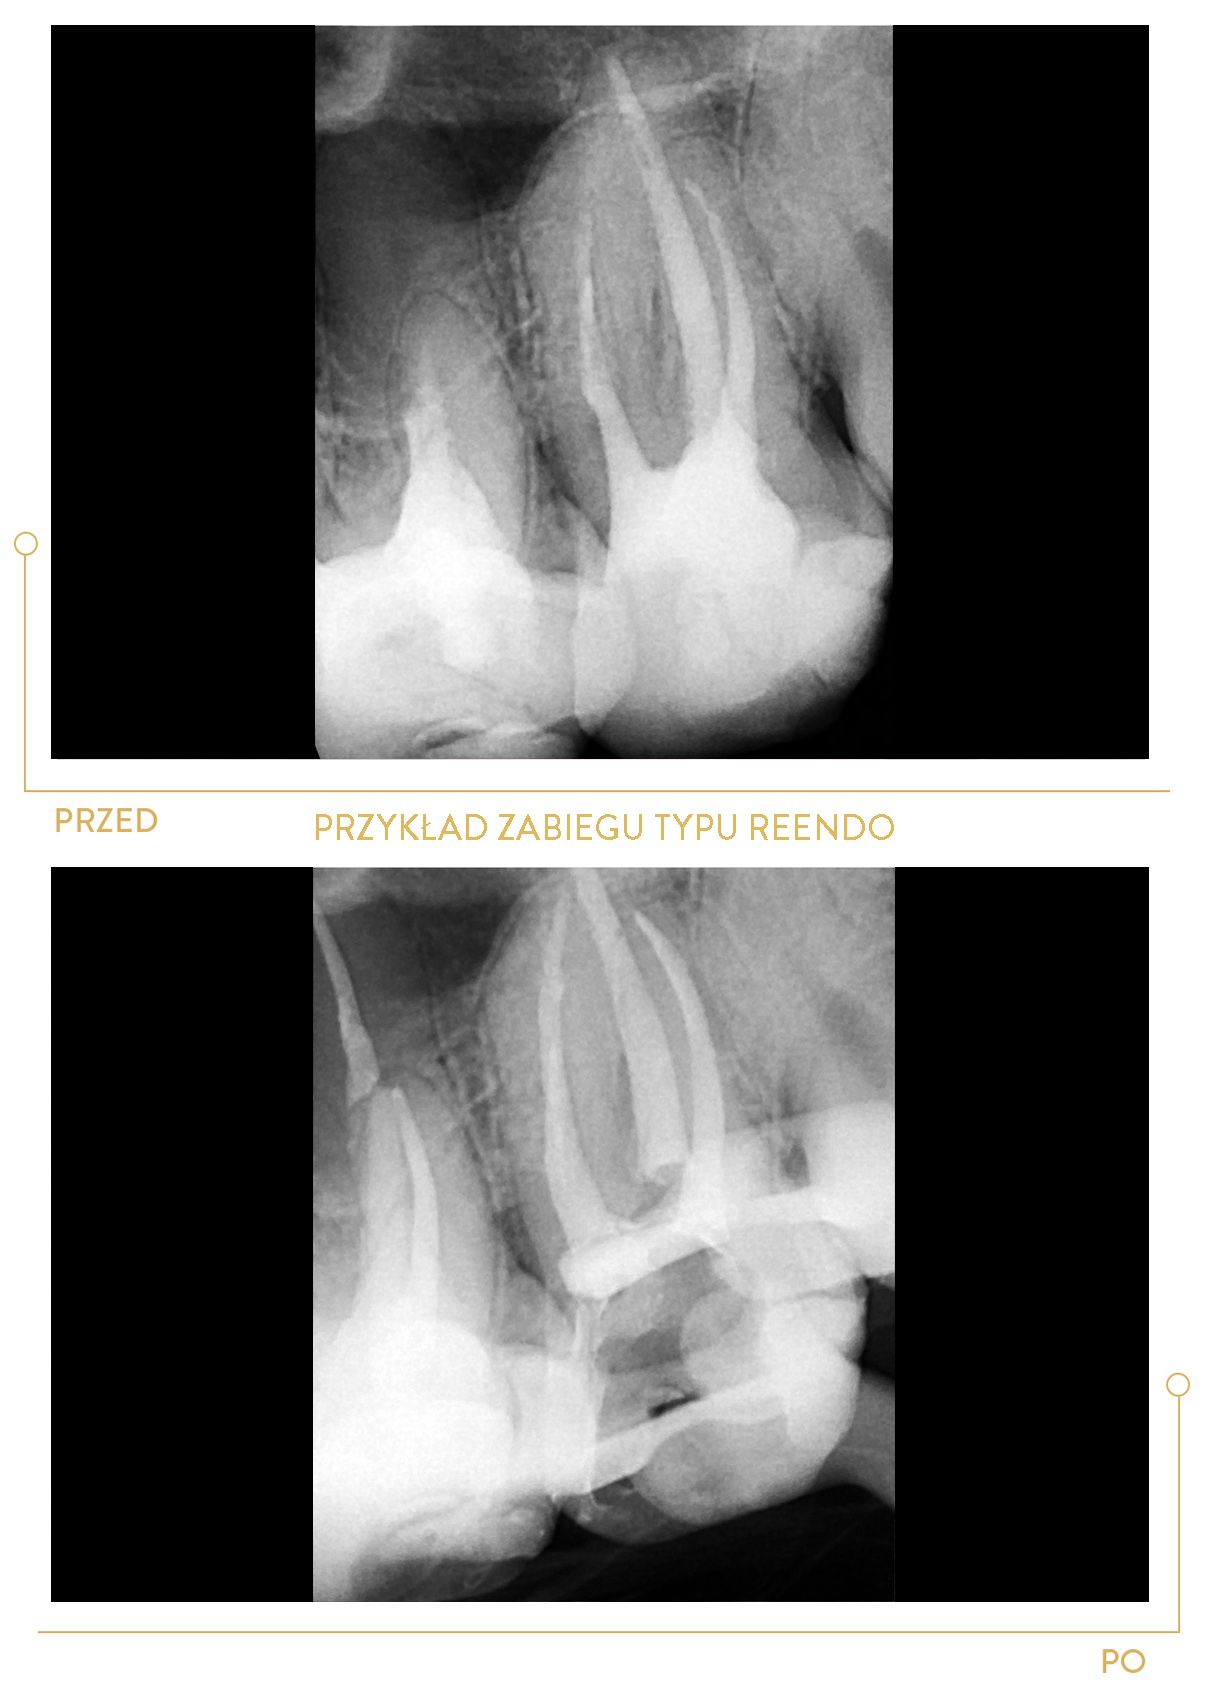

Dzięki ciągłemu rozwojowi zawodowemu do jej kompetencji należy również nowoczesne leczenie endodontyczne pod mikroskopem. W Centrum Stomatologii Cichoń realizuje swoje pasje zawodowe, szczególnie w obszarach:

Duża ambicja, ciekawość i zaangażowanie sprawiają, że dąży do pogłębiania wiedzy w wielu dziedzinach stomatologii, ze szczególnym uwzględnieniem endodoncji.

Doktor Magda Grabowska to lekarz o wielkim doświadczeniu. Była moją ostatnią nadzieją jeżeli chodzi o uratowanie mojego zęba. Była to 3 więc tym bardziej jestem jej wdzięczny. Ząb przeleczony kanałowo pod mikroskopem z pełną precyzją. Pani doktor bardzo dziękuję!

Doktor Magda jest niewątpliwie najlepszym specjalistą w leczeniu kanałowym. Ząb którego żaden z lekarzy nie był w stanie udrożnić pani doktor wykonała powtórne leczenie kanałowe na jednej 1,5 godzinnej wizycie które zakończyło się odbudowa estetyczna . Po ogromnych zmianach zapalnych nie ma śladu . Dziękuje z całego serca .

Dr Magda uratowała mojego bolącego zęba przeznaczonego do usunięcia... Jej spokój i profesjonalizm i dokładność po prostu mnie powaliły. Nie wiem jak to jest, że w jednym miejscu każą zęba usunąć, a w innym okazuje się, że da się go uratować. Po wizycie miałam porównanie - chodzi o wiedzę i doświadczenie. Dr Magda to definitywnie lekarz godny polecenia, szczególnie do ciężkich przypadków.